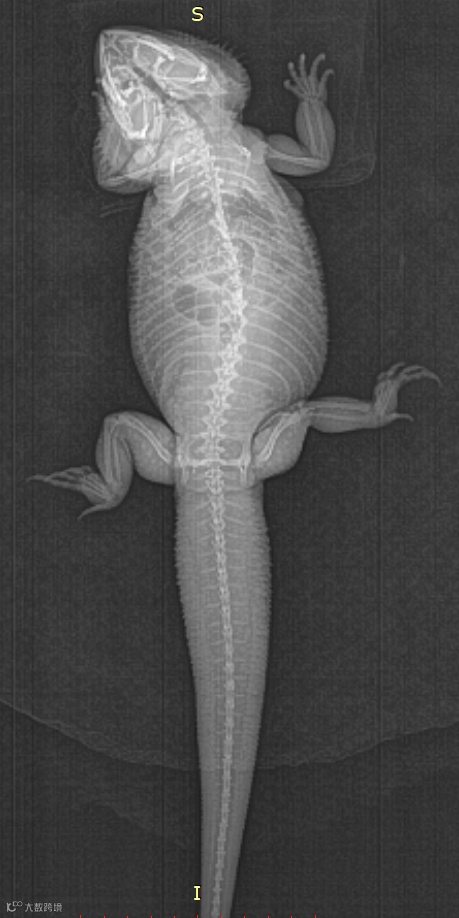

提升诊断精度:赛诺威盛动物CT集合了中国智慧和创新精神,采用先进的成像技术、智能的后处理应用和标准化的操作设计。可清晰捕捉动物的细微结构,为动物医疗提供精准、清晰的影像诊断,对珍稀物种研究具有突破性意义。

降低运营成本:赛诺威盛动物CT专属的动物影像链技术,为不同体型和重量的动物量身打造智能化扫描剂量调节模式,减少耗电量,减少球馆损耗,降低运营成本。